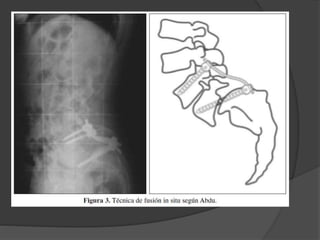

 Espondilolistesis deAlto Grado - Artrodesis in situ - Descompresión y artrodesis posterior - Reducción artrodesis 360 - Resección de L5 y APL L4 – S1